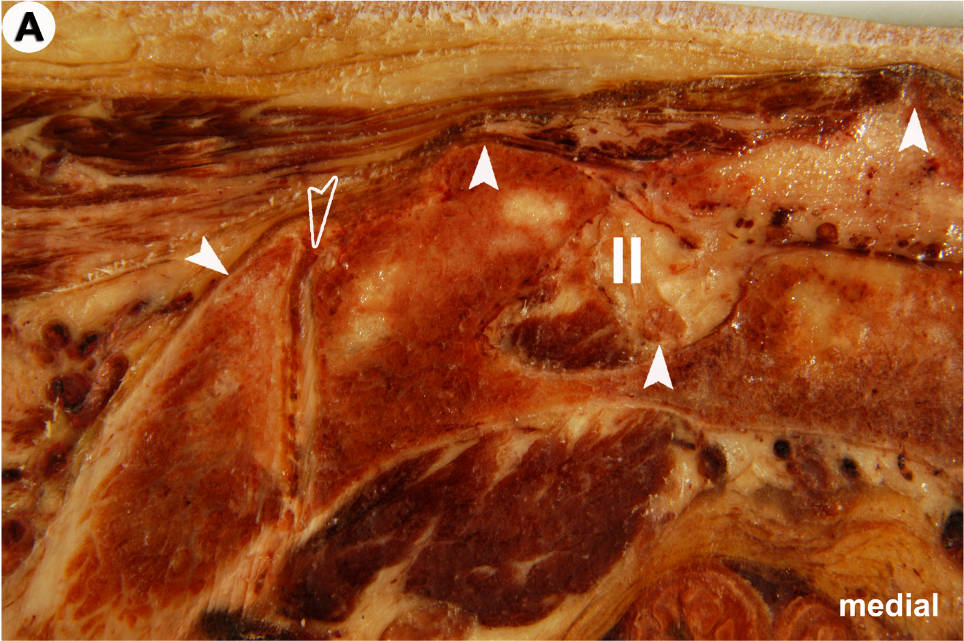

Anatomischer Transversalschnitt (A) und korrespondierendes US-Bild (B) auf Ebene des Foramen sacrale posterius secundum (II): Grundlage für die US-gezielte Injektion des Iliosakralgelenkes (ISG).

In der US-Darstellung ist der dorsalste Anteil des ISG einsehbar (offener Pfeilkopf). Der Spalt entspricht dem radiologischen Gelenkspalt! Die knöchernen Landmarken (gefüllte Pfeilköpfe) sind aber in allen Details deutlich zu erkennen (von medial nach lateral): Crista sacralis mediana, II, Crista sacralis lateralis, Facies glutea ossis ilii.